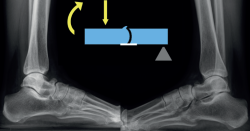

La mayoría de las coaliciones atípicas se diagnostican como hallazgos casuales al solicitar radiografías simples en pacientes con dolores en los pies, generalmente con deformidad en plano valgo. Las proyecciones convencionales –dorsoplantar y lateral– de ambos pies en carga suelen poner ya de manifiesto coaliciones atípicas como las talonaviculares y las calcaneocuboideas. Las proyecciones oblicuas son importantes porque suelen mostrar algunas coaliciones como las naviculocuboideas, las cuneometatarsianas y las coaliciones tarsales masivas. Las radiografías de ambos tobillos en carga suelen mostrar la consecuencia de algunas coaliciones tarsales masivas en forma de tobillo en cúpula (ball-and-socket)(13). Se han descrito varios signos radiológicos asociados a las coaliciones atípicas, como el “signo de la seta” en las talonaviculares, aunque algunas coaliciones atípicas presenten signos ya conocidos en las típicas, como el talar beak en las calcaneocuboideas o el del “oso hormiguero” en las naviculocuboideas(14) (Figura 1).

mact.1701.fs2403007-figura1.png

Figura 1. Radiografías en proyección lateral de unos pies en carga. Se aprecia una coalición calcaneocuboidea bilateral. La función hace la forma y la forma hace la función, por lo que se observa un osteofito dorsal talar (talar beak) con forma de articulación calcaneocuboidea. Esta disposición adaptativa permite a la articulación talonavicular funcionar también como una calcaneocuboidea.